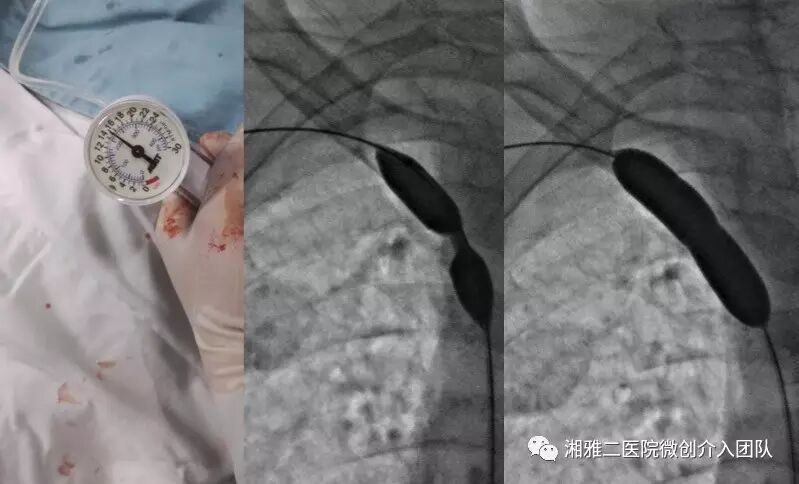

使用高压注射器造影

6,锐器再通后,在球囊扩张前应常规行穿刺再通通路造影,明确再通道在血管真腔内,方可球囊扩张。如果进入肺目标区域,如动脉或者胸腔,则应该立刻使用弹簧圈栓塞再通道。再通完成后行球囊扩张

每次扩张约30秒。扩张次数为“腰征+1”。然后通过血管鞘侧管造影